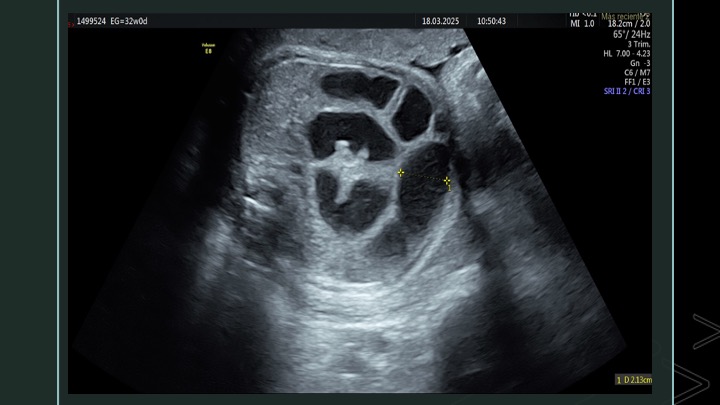

Se presenta el caso de una paciente de 23 años de edad, secundigesta, sin antecedentes personales ni familiares de relevancia. La paciente adjunta el estudio de screening de aneuploidías de la semana 11-14, que arroja bajo riesgo. Las imágenes 1 y 2 describen los hallazgos identificados durante la evaluación de la anatomía fetal en la semana 12. Las imágenes 3, 4 y 5 corresponden a los controles ecográficos posteriores, del segundo y tercer trimestre. La imagen 6 muestra al recién nacido. Seleccione la opción correcta: A. Corresponde a una hernia umbilical fisiológica con resolución más tardía. B. Corresponde a una gastrosquisis con cierre espontáneo intraútero. C. Corresponde a un onfalocele con ruptura del mismo. D. El defecto de pared cerró espontáneamente mejorando el pronóstico y riesgo de complicaciones gastrointestinales. Figura 1: se visualiza corte axial del abdomen fetal, a nivel de la inserción del cordón umbilical, con Doppler color en semana 12. Figura 2: se observa corte axial, a nivel de la inserción del cordón umbilical en la pared abdominal anterior, en semana 12. Figura 3: corte sagital a nivel de la inserción del cordón en la pared abdominal anterior, con Doppler color, en semana 20. Figura 4: corte axial del abdomen fetal, en semana 32, donde se identifica dilatación de las asas intestinales. Figura 5: corte axial del abdomen fetal, en semana 32, donde se identifica dilatación de las asas intestinales, con la utilización del Doppler color. Figura 6: se observa al recién nacido.

A partir de ese momento se realizó un seguimiento ecográfico exhaustivo, evidenciándose una dilatación progresiva del intestino intra-abdominal, entre 10.5 mm en semana 25 (Figura 4) a 26.5 mm en semana 34, siempre con aparente indemnidad de la pared abdominal (Figura 5). La progresión biométrica fue acorde a la edad gestacional, con Doppler fetoplacentario y valoraciones de líquido amniótico normales. En el último control ecográfico de la semana 34, el equipo de obstetricia, en conjunto con neonatología, deciden la finalización del embarazo por cesárea abdominal. El recién nacido fue de sexo masculino, con un peso de 2760 gs, adecuado para la edad gestacional, Apgar 6/8, y al examen físico presentó indemnidad de la pared abdominal anterior  (Figura 6). Se realiza una ecografía abdominal y radiografía de abdomen, confirmando la dilatación intestinal generalizada (Figura 7).  A las 72 horas de vida, se realiza laparotomía exploradora donde se identifican asas intestinales obstruidas a nivel de íleon y colon derecho por lo que se procede a la resección de las mismas con reconstrucción del tránsito mediante la anastomosis yeyuno colónica término-lateral y yeyunostomía en fosa ilíaca derecha. Actualmente, se encuentra en seguimiento por servicio de cirugía y gastroenterología pediátrica.